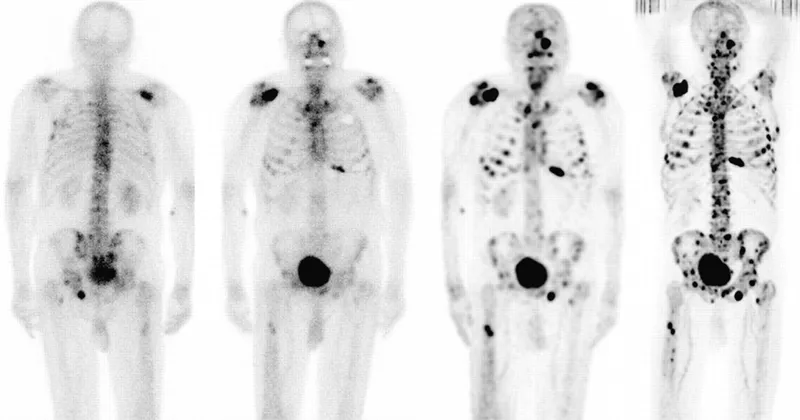

- Bone Scan (Tc-99m): Sensitive for blastic activity; multiple lesions.

- PET-CT: Lytic lesions, staging, response.

- Bone scan for screening; biopsy for definitive diagnosis. X-ray is initial imaging.